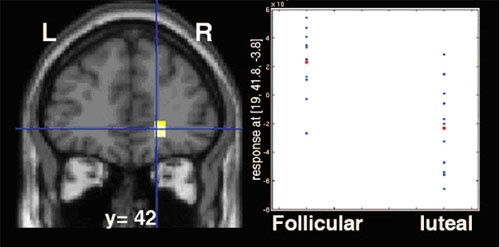

Brain activity in the orbitofrontal cortex (yellow), part of the brain's reward system, was increased during women's pre-ovulatory (follicular) menstrual phase compared to their-post-ovulatory (luteal) phase while they were anticipating winning money. Located just behind the eyes, this area is thought to regulate emotion and reward-related planning behavior. Functional MRI data superimposed on structural MRI scan.

The fMRI pictures showed that the reward system responded differently when women anticipated a reward compared with when the reward was actually delivered, depending upon their menstrual phase.

When they hit the jackpot and actually won a reward, women in the pre-ovulatory phase activated the striatum and circuit areas linked to pleasure and reward more than when in the post-ovulatory phase.